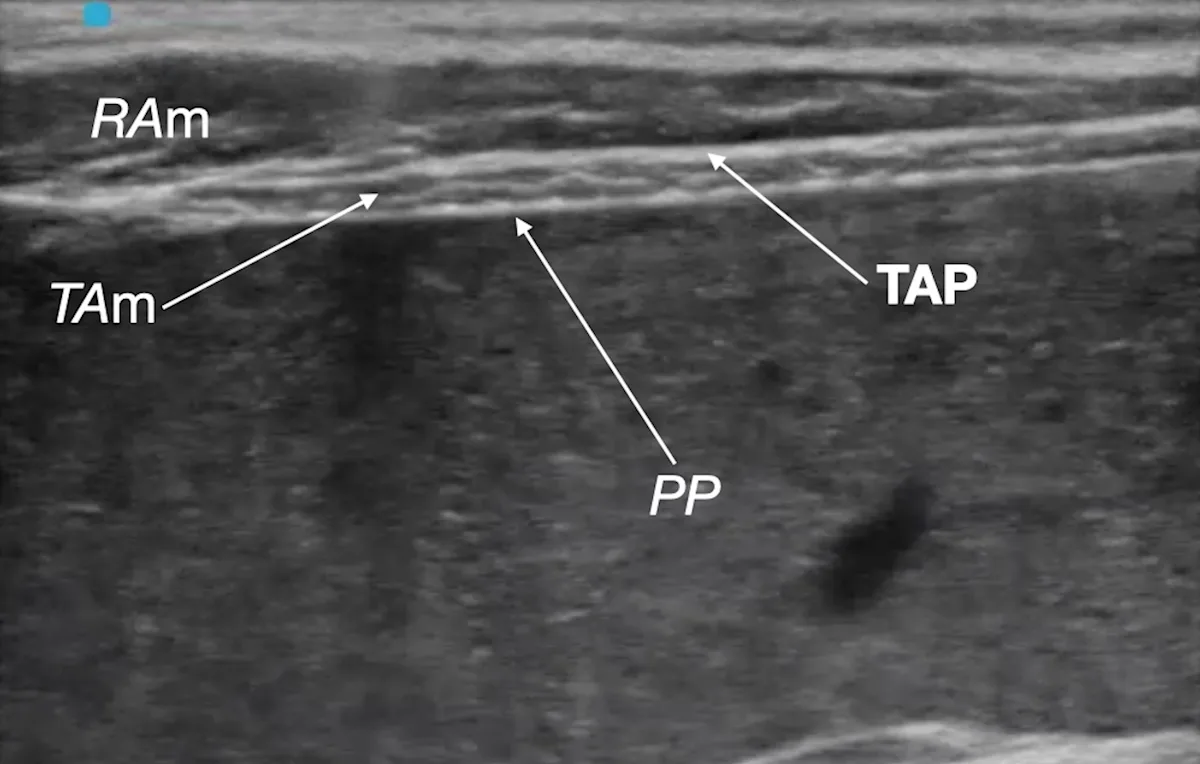

Step 8: Identify the Target Plane

Identify the target fascial plane (ie, TAP) as a hyperechoic line between the rectus abdominis muscle (RAm) and transversus abdominis muscle (TAm).

PP, parietal peritoneum